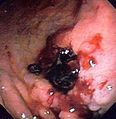

Gastric ulcer in antrum of stomach with overlying clot due to gastric lymphoma.